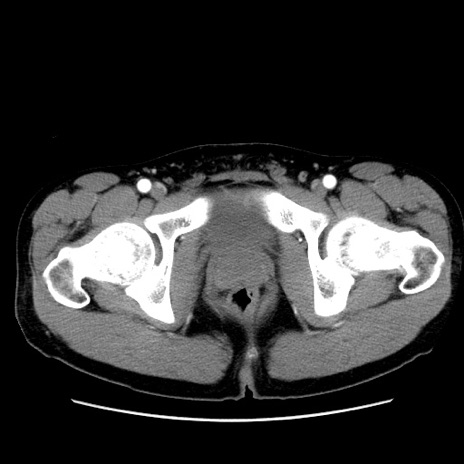

症例36(横断像)

【症例】20歳代 男性

【主訴】心窩部痛

【現病歴】今朝より上腹部痛あり。一旦軽快していたが再度出現したため救急要請。昨日夕に白身の魚を含む刺身を食べた。

【身体所見】BP 136/89mmHg、HR 74/min、BT 37.0℃、腹部:膨満、軟、心窩部に圧痛あり。反跳痛なし、筋性防御なし、腸雑音やや亢進あり。

【データ】WBC 17700、CRP 0.48